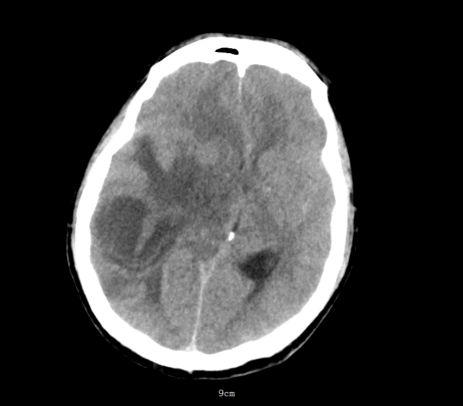

凌晨5点,神经医学科突然响起急促的电话铃声。“有一名48岁男性患者突发昏迷!双侧瞳孔已散大到5mm,对光反射消失,CT提示右侧颞顶枕叶巨大占位性质待查,中线结构明显移位,考虑脑脓肿或脑肿瘤合并脑疝!”电话那头,急诊医生语气急促。

影像医学科王樱花主任阅片后,考虑脑脓肿合并急性脑疝。脑疝是颅内压增高最危险的并发症之一,堪称大脑“断电”前兆。当颅腔内某一部分压力骤增,脑组织被挤压到另一个腔室,压迫脑干,可迅速导致呼吸心跳停止。而脑脓肿是一种由细菌、真菌或寄生虫引起的颅内化脓性感染,若不及时处理,脓肿增大压迫脑干,后果不堪设想。

该患者MR显示:右侧顶枕叶类圆形低密度影,周围水肿明显,中线结构左移超过1cm脑室受压变窄,环池显示不清,提示小脑幕切迹疝早期,已处于濒死边缘。